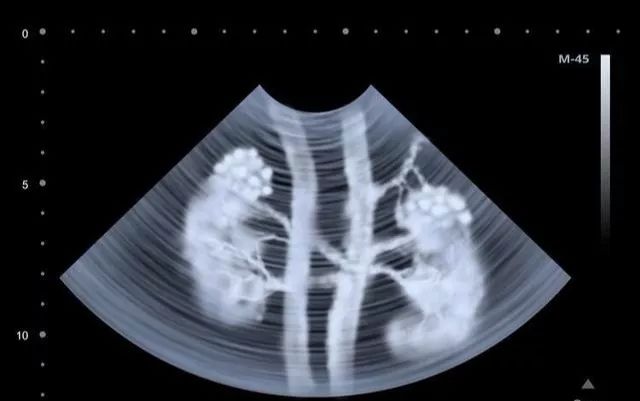

治疗显示,静脉内注射的MSCs能够迁移到急性和慢性肾损伤模型动物的肾小球、肾间质、小管周围血管和肾小管。

移植干细胞进入人体后,干细胞会通过“迁徙”和“归巢”的诱导作用下到达受损的肾脏,这些移植的干细胞一方面能够根据周围微环境分化成新生的肾脏功能细胞;

干细胞植入体内后,通过干细胞的自动归巢作用,干细胞会自动转移到肾脏病灶,分化生成所需的各类细胞,从而达到修复肾脏固有细胞,恢复肾功能,重建肾脏血液循环,阻断和逆转肾脏纤维化进程。   近年来干细胞在治疗肾病过程中发现,干细胞可分化成肾固有细胞,肾实质细胞等,所以干细胞移植后对肾脏功能具有良好的修复和重建作用。